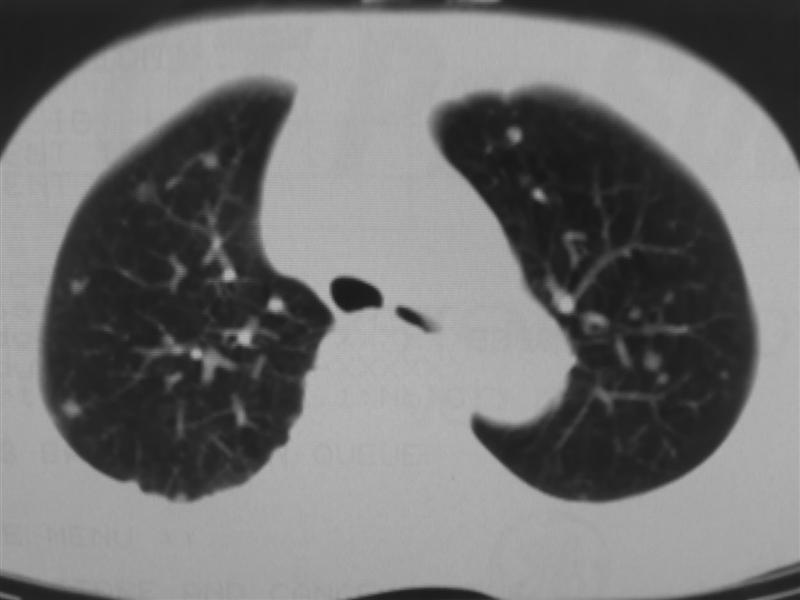

标题: CT10080:F76Y,各位老师发表高见!!! [打印本页]

标题: CT10080:F76Y,各位老师发表高见!!!

支持右下肺癌伴肺内转移

右下肺周围型肺癌伴双肺右侧叶间 胸膜及右肺门淋巴结转移

肺癌伴肺、胸膜转移